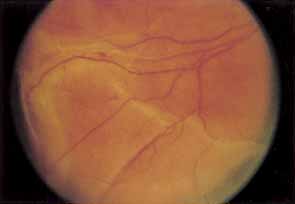

Two types of diabetic retinal detachments occur, those that are caused by traction alone (nonrhegmatogenous) (Fig. 14), and those caused by retinal break formation (rhegmatogenous) (Figs. 15 and 16). Characteristics of nonrhegmatogenous (traction) detachment in PDR include the following: (1) the detached retina is usually confined to the posterior fundus and infrequently extends more than two-thirds of the distancd to the equator, (2) it has a taut and shiny surface, (3) it is concave toward the pupil, and (4) there is no shifting of subretinal fluid.

Fig. 14 Traction retinal detachment. The detached retina has a smooth noncorrugated appearance and is convex toward the pupil.

Fig. 15 Combined traction/rhegmatogenous retinal detachment. The detached retina has a corrugated appearance and is concave toward the pupil.